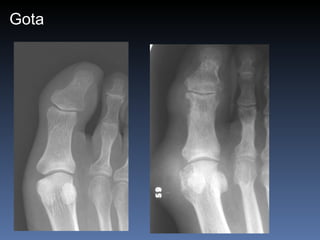

Gota Asimetrica Mas comun en la 1a.  articulacion M.T.T.F. Es comun la bursitis del olecranon Erosiones con bordes sobresalientes (mordedura de rata) Edema de partes blandas Depositos con densidad de tejidos blandos (tofos)

Gota